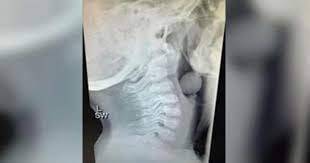

Avustralyalı bir anne olan Angela Henderson, sosyal medyada paylaştığı gönderisiyle bu duruma dikkat çekti. Gördüğünüz röntgen, 5 yaşındaki bir çocuğun yemek borusuna ait. Röntgene dikkatlice baktığınızda çocuğun yemek borusuna yuvarlak bir cismin takıldığını görüyorsunuz. Çocuk, boğazına takılan üzüm tanesinin yemek borusunu tamamen tıkamadığı için şanslıydı.